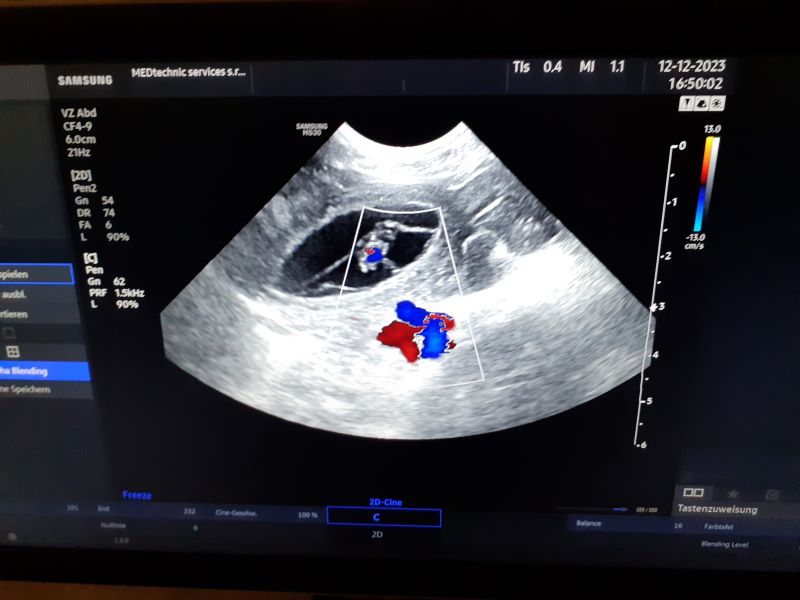

heartbřezost Aneli potvrzena

- předpokládaný termín vrhu 15. ledna 2024

- dne 14. 11. 2023 proběhlo plánované krytí naší Aneli s Irwinem, a tak netrpělive vyhlížem termín potvrzujícího ultrazvuku wink Vzhledem k jejímu včerejšímu chování na honu, věřím tomu, že to dopadlo. Pracovla jen tak na oko. ale vypadalo to, že kdyby se rozdávala cena za mazlení, tak tu by určitě vyhrála heart.